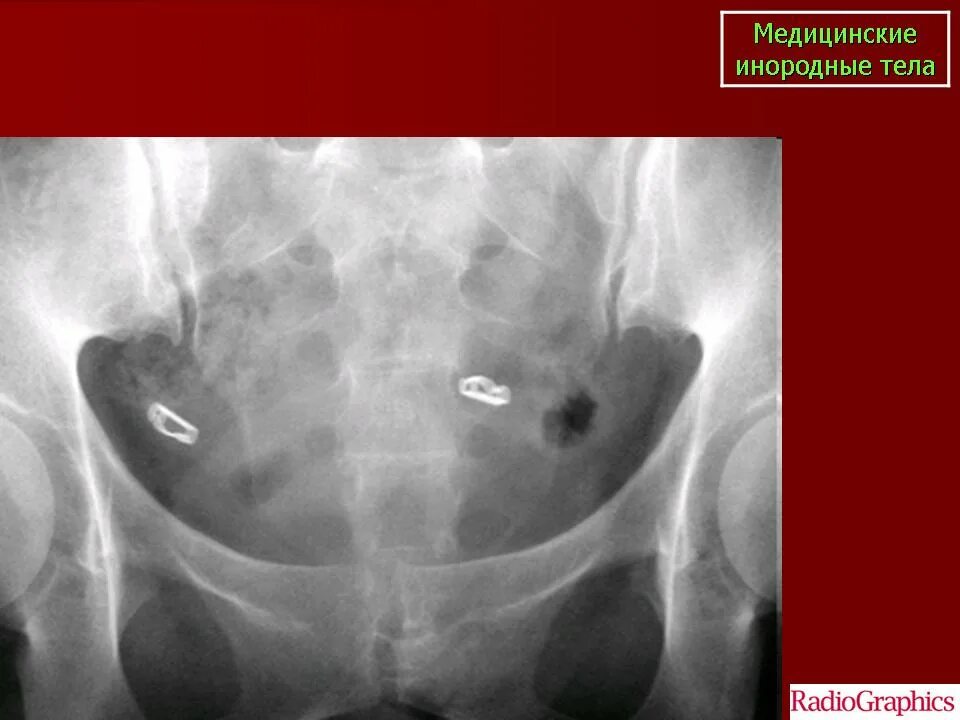

Инородным телом лечение инородного тела